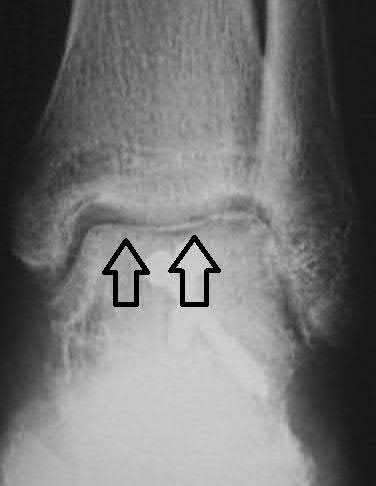

A 25-year-old male sustains an ankle fracture dislocation and undergoes open reduction and internal fixation. He returns to clinic five months following surgery complaining of continued ankle pain and instability with weight bearing. His immediate post-operative AP radiograph is seen in Figure A. Which of the following could have prevented this patient from developing persistent pain?

The patient presents with continued ankle pain and instability following open reduction and internal fixation. The radiograph in figure A demonstrates inadequate restoration of fibular length, likely leading to continued tibiotalar instability.